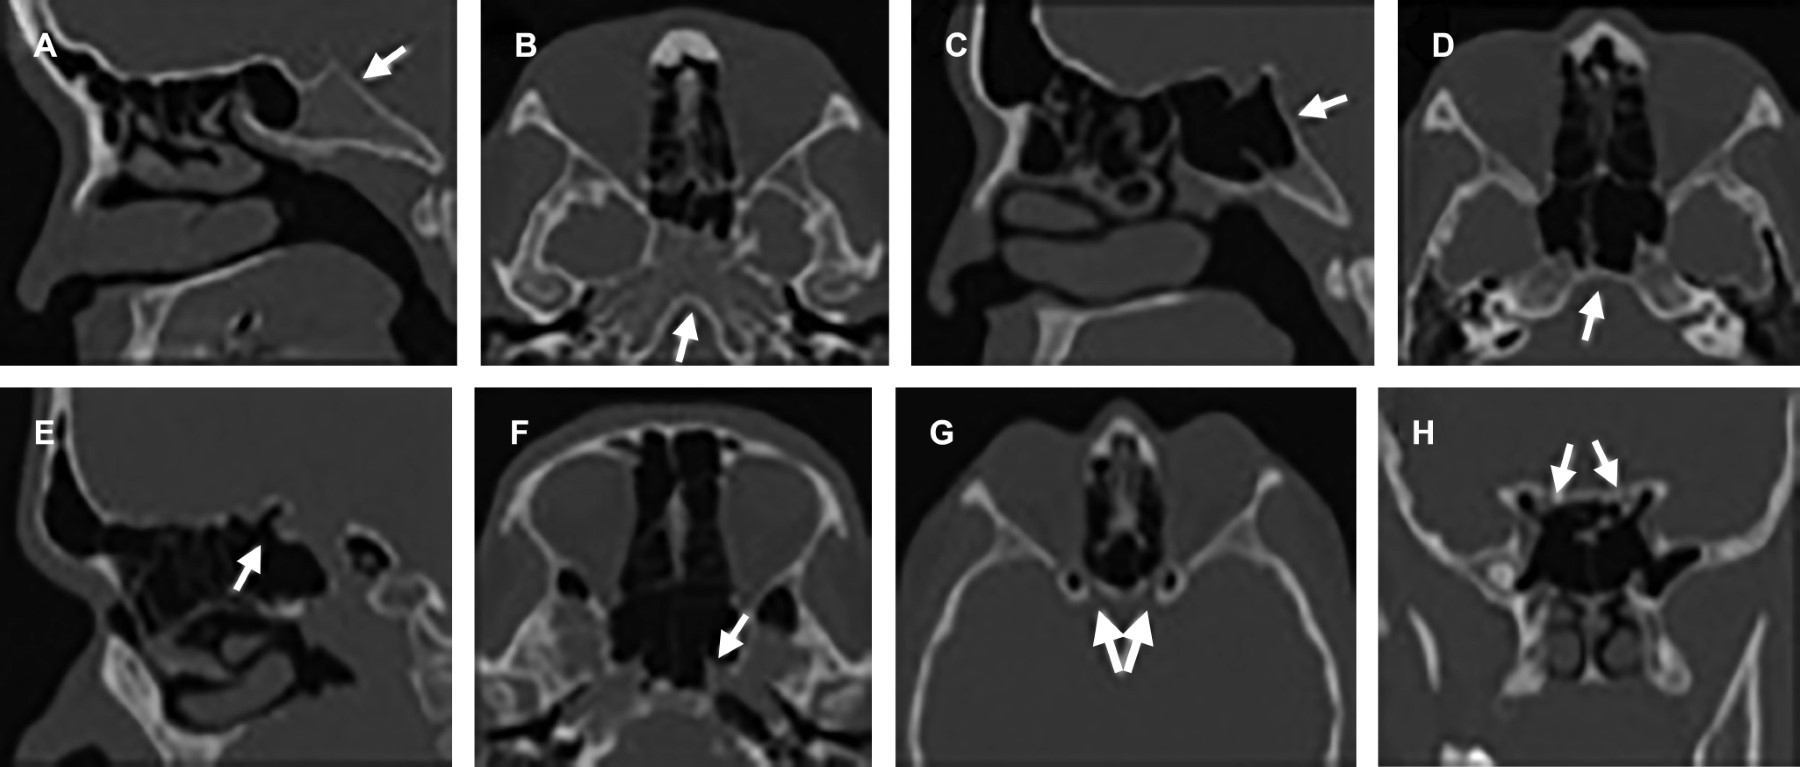

En cuanto a la conformación de las celdillas etmoidales, la neumatización supraorbitaria (superior a la hendidura etmoidal) se encontraba presente en 46% de los pacientes estudiados, mientras que la neumatización adyacente al ostium del antro maxilar y a lo largo del piso de la órbita (celdillas infraorbitarias o de Haller) se observó en 10% (Figura 3). La celdilla de Onodi, definida como celdilla etmoidal posterior que se extiende al margen superior y lateral del seno esfenoidal, se visualizó en 12% de los estudios (Figura 3). La celdilla de agger nasi comprende la neumatización del dorso nasal, anterior a la inserción del cornete medio y corresponde a la variante estudiada más frecuentemente encontrada en hasta 95% (Figura 1).

La desviación de la lámina papirácea y estructuras de la órbita hacia el seno etmoidal entendida como prolapso orbitario se encontró en apenas 2% de los pacientes (Figura 3).

La neumatización supraortbitaria descrita como neumatización de celdillas etmoidales por arriba de la hendidura etmoidal predispone a lesión de la arteria etmoidal anterior (rama de la arteria oftálmica), en los casos en los que ésta viaje libre dentro del seno etmoidal, presentándose en aproximadamente 26-35% de la población general2,8 y 46% de la población estudiada. Esta variación se pudiera asociar a la manera de cuantificar su presencia de forma unilateral o bilateral en pacientes individuales, cuestión que no fue apartada en el presente estudio. Su lesión condiciona un hematoma retroorbitario por retracción del vaso al seccionarlo de forma inadvertida.

Las celdillas etmoidales infraorbitarias, también conocidas como "celdillas de Haller", se describen como celdillas etmoidales que se proyectan por debajo de la bulla etmoidal a lo largo del piso orbitario, identificada en 10% de nuestra población y descrita en población general entre 3 y 20%,7,9 variación probablemente secundaria a diferencias conceptuales. Cuando no se identifican y resecan durante el procedimiento quirúrgico pueden condicionar fracaso de la antrostomía maxilar.6

Las celdillas esfenoetmoidales o "celdillas de Onodi" son celdillas etmoidales posteriores que se extienden posterosuperior respecto a la pared anterior del seno esfenoidal, condicionando que se modifique el trayecto de arteria carótida interna y nervio óptico y predisponiéndolas a lesiones inadvertidas durante el procedimiento quirúrgico. Se identificaron 24 pacientes en nuestra población (12%), similar a lo reportado en la literatura (8 a 14%).6,10

La celdilla etmoidal más anterior, que se extiende anteriormente en el hueso lacrimal, también recibe el nombre de "celdilla de agger nasi". Superior a la misma, se puede identificar diverso número y grado de neumatización de celdillas frontoetmoidales. Su relevancia radica en que provee un acceso quirúrgico al ostium primario del seno frontal y su resección permite permeabilizar el drenaje, en los casos en los que exista patología del mismo. Wormald y colaboradores mencionan y validan la clasificación de "International Frontal Sinus Anatomy Classification (IFAC)" para describir las variantes anatómicas de la región frontal previo a cirugía endoscópica funcional,11 para con ello disminuir la necesidad de reintervención o persistencia de sintomatología. Se identifican en aproximadamente 3 a 100% de los pacientes, margen amplio a causa de su definición operacional.6,12 En nuestra población se utilizó el concepto anteriormente mencionado, identificándolas en 95% de los estudios. Por ello es imperativo no sólo reconocerlas, sino profundizar en la descripción del grado de neumatización y relación respecto al ostium de drenaje del seno frontal en el reporte tomográfico.